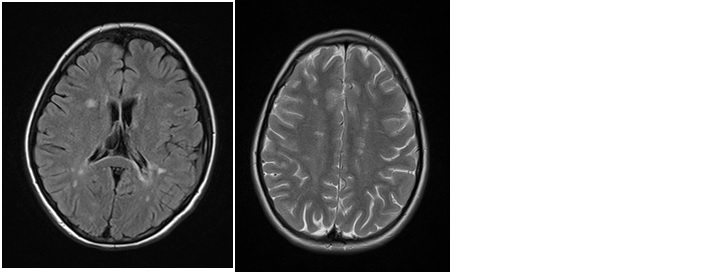

W diagnostyce neurologicznej ważne są badania neuroobrazowe. Poniższe obrazy rezonansu magnetycznego (MR) głowy mogą odpowiadać zmianom w przebiegu: